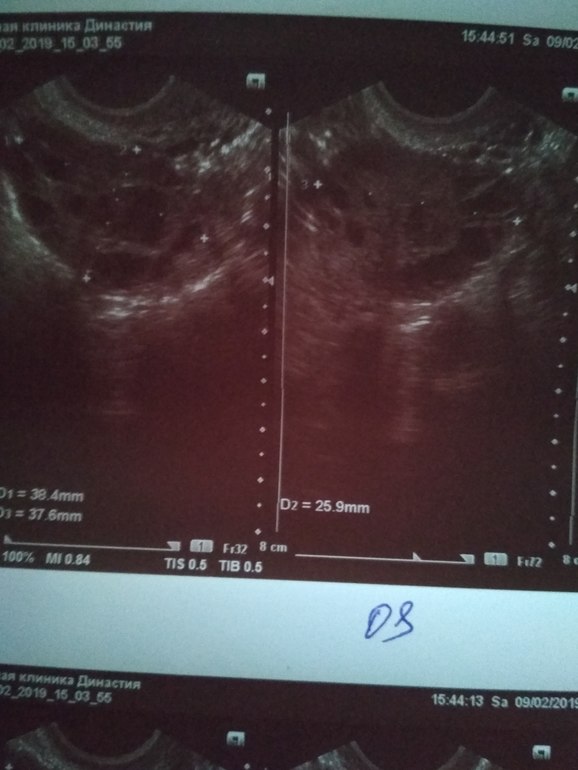

9.02.19 18 ДЦ - 36,6 ( в этот день не выдержала пошла на фолликулометрию...,там мне сказали,что овуляция у меня была...когда непонятно...делала тесты на овуляцию 2 полоска была призрачная...делала тесты с 4.02.19 по 8.02.19 как положено по инструкции. По фолликулометрии вот что сказали: Эндометрий 5 мм однородный,повышенной эхогенности..., в левом яичнике кистозное желтое тело 18*14 мм со слабым кровотоком по периферии (врач узист сказал,что в желтом теле есть немного крови...я ее спросила почему так?? Она толком не ответила,сказала типа нечего страшного так бывает...)., свободная жидкость в позадиматочном пространстве: "следы" жидкости.,ЗАКЛЮЧЕНИЕ: несоответствие эндометрия дню цикла. Овуляторный цикл. Мультифолликулярная эхоструктура яичников.)

Жёлтое тело в левом яичнике